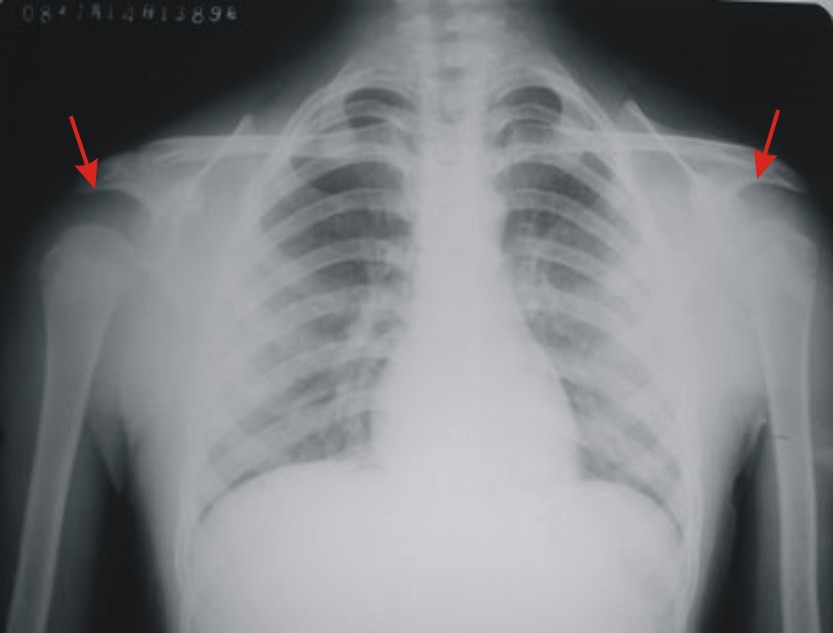

患者,男,13岁。自诉两月前双肩关节时有弹响,有时左、右肩关节轮换隐痛。但双上肢能抬举、左右旋转、屈伸自如。pe:双肩及双上肢皮肤无红、肿。触诊:双肩关节区域有抖动,似触心脏的搏动感,但抖动、搏动感能自控。双肩区域皮肤无发热。听诊:用耳贴近患者双肩区能听到弹响声。x线胸部后前位示:双肩关节间隙增宽,考虑双肩关节半脱位。双肩关节正侧位片示:双肩关节无明显脱位征象。双肩关节区域透视示:双肩关节解剖位时,双肩关节间隙增宽(与胸部后前位的双肩关节间隙相等),也能见双肱骨头在双肩关节腔内上、下移动约1cm左、右。但患者能自控(双肱骨头在双肩关节腔内不上、下移动)。请战友们详见患者相片、胸部后前位片、双肩关节正侧位片。我第一次碰到这样的病例(是否是神经性关节病“夏科氏关节”?),经验不足,希望能帮助诊断。亦请分析病因、病理机制,是什么原造成的?最好能提供治疗方法,谢谢!

双侧肩关节解剖位时,双肩关节间隙增宽,但肱骨头及周边骨质 关节腔均未见异常。与骨科专家会诊结果,目前只能诊断:肩关节松弛症!

双肩关节间隙增宽,但肱骨头及周边骨质 关节腔均未见异常。